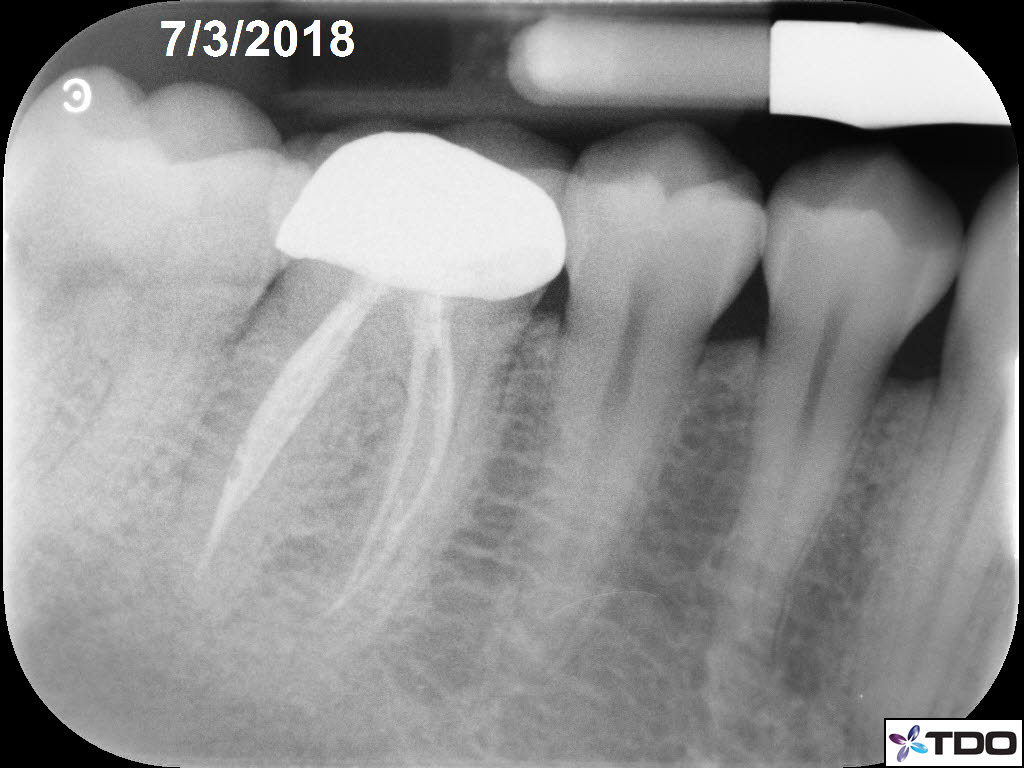

In the hierarchy of dentin conservation the existing restorative has the lowest priority and it quite frankly gets in the way of our access to the root canal system. But, after practicing directed dentin conservation for a while, you sometimes get lucky. The patient is 40yo. She was symptomatic at the time of treatment and interestingly the mesiobuccal canal was partially vital while the mesiolingual, distobuccal and distolingual canals were partially necrotic. She was asymptomatic at the completion visit as well as at the follow-up appointments.

Great insight into the challenges of dentin conservation Dale. The case illustrates the unpredictability of canal vitality and the need for a strategic approach. The 1 year follow up success adds another layer to the discussion. Professional General Contractors in Laval Quebec CA

Great insight into the challenges of dentin conservation Dale. The case illustrates the unpredictability of canal vitality and the need for a strategic approach. The 1 year follow up success adds another layer to the discussion.